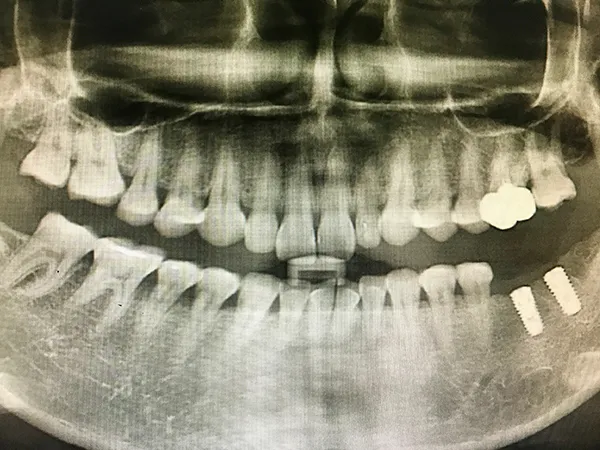

임플란트는 치아를 상실했을 때, 치아의 기능과 심미성을 회복하기 위해 사용하는 치과 치료 방법입니다. 임플란트는 인공 치아 뿌리를 잇몸뼈에 삽입한 후, 그 위에 인공 치아를 장착하는 방식으로 진행됩니다. 이는 자연 치아와 유사한 기능과 외관을 제공하며, 장기적으로 안정적인 결과를 보장합니다.

임플란트 시술은 몇 가지 단계를 거칩니다. 먼저, 환자의 구강 상태를 점검하고, 임플란트를 식립 가능한지 확인을 합니다. 그다음, 임플란트 뿌리를 잇몸뼈에 삽입하는 수술을 진행합니다. 수술 후에는 몇 개월 동안 임플란트가 뼈에 잘 고정되도록 기다리는 과정이 필요합니다. 마지막으로, 임플란트 위에 인공 치아를 장착하여 시술을 마무리합니다.